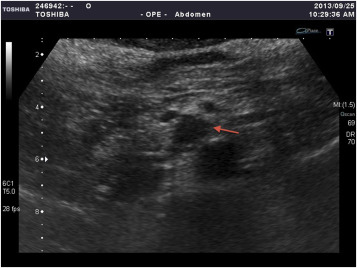

Magnetic resonance imaging with contrast enhanced (T2 weighted) revealed an ...

Magnetic resonance imaging with contrast enhanced (T2 weighted) revealed an enhancing lesion (arrow) in the uncus of the pancreas.